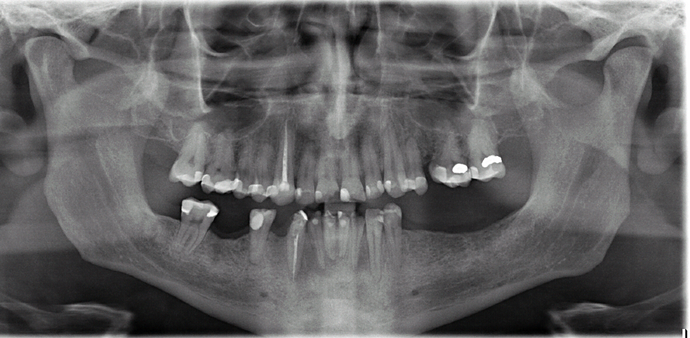

All-on-4/ Full Mouth Dental Implants / Teeth in a Day: Case 18- Upper crowns and Lower All-on-4 Bridge

This patient, a mental health counselor was frustrated that despite taking care of his teeth all his life, he ended up having several cavities that made him lose several of his lower teeth. His cavities in his upper natural teeth was manageable through crowns and his remaining lower teeth were extracted and new implants and teeth were installed in one day without the need for any bone grafting.

Procedures : extractions, implants, All on 4 , Teeth in a day, no bone grafting and full mouth reconstruction with monolithic zirconia bridges.